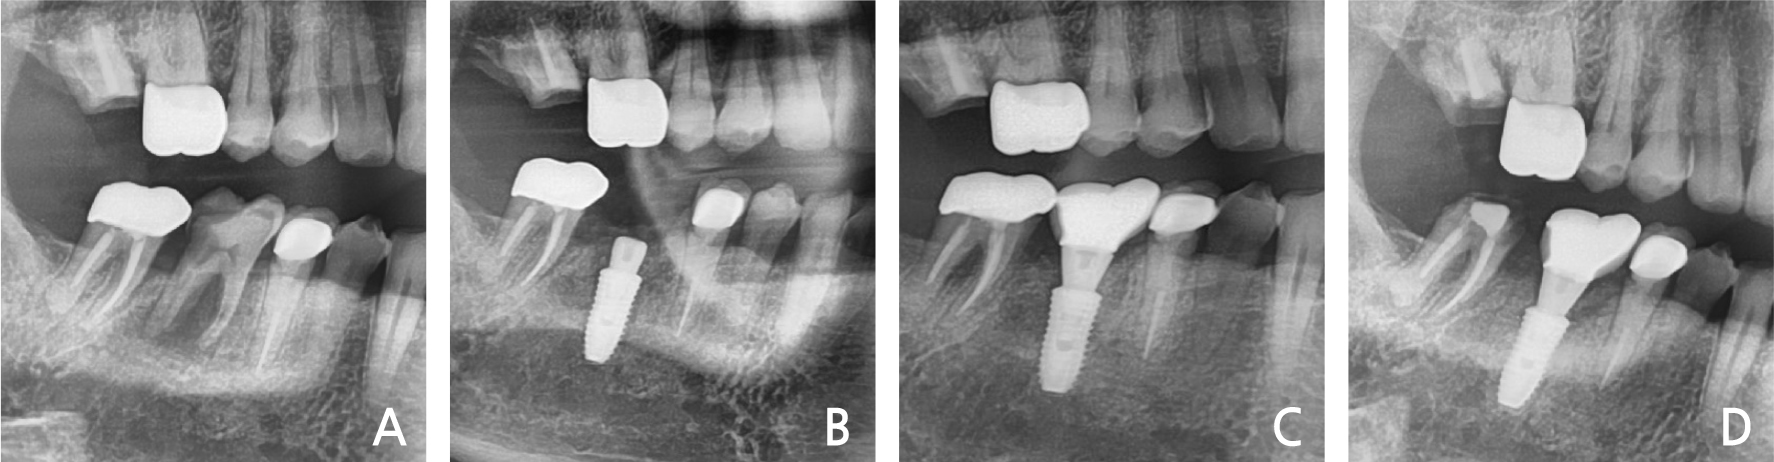

Clinical and radiological evaluation revealed severe mobility of the left maxillary 2nd molar and a cystic lesion in the crown area of the left maxillary 3rd molar (Fig. 1A). Spontaneous bleeding, purulent exudate, and periodontal abscesses were observed. He had no history of systemic disease. Under local anesthesia, a three-sided flap was elevated and the 2nd molar & 3rd molars were extracted. The cystic lesion was removed and immediate implant placement with sinus elevation (lateral approach) was performed (Fig. 1B). The primary anchorage was provided by the inferior wall of the sinus. After two months, loading was performed (Fig. 1C). In the 3-years follow-up, the bone & implant was intact (Fig. 1D).